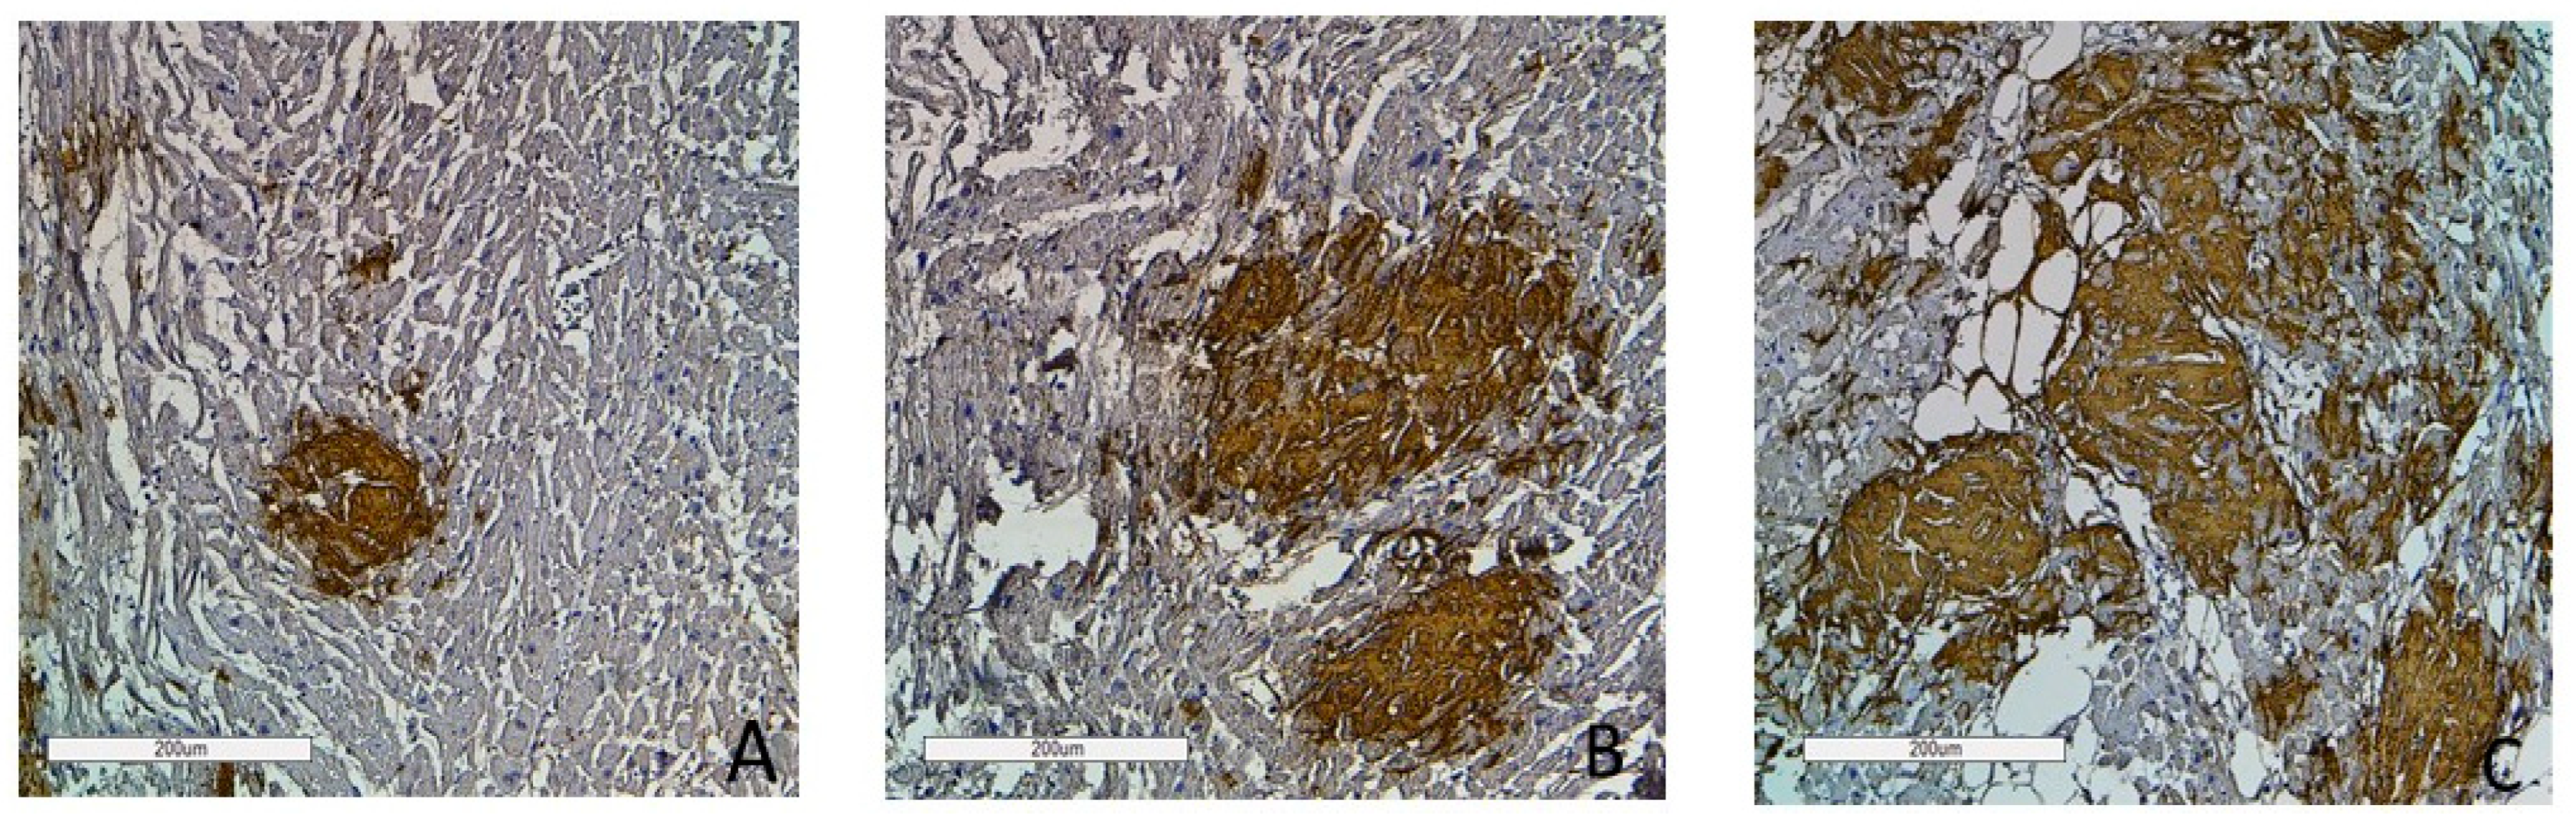

Figure 9.

Immunohistochemistry images of amyloid deposition in the myocardium. Grade 1 (0–20% of amyloid deposits) (A); Grade 2 (20–40% of amyloid deposits) (B); Grade 3 (more than 40% of amyloid deposits) (C). Amyloid is stained with polyclonal antibody to Prealbumin, ×100.